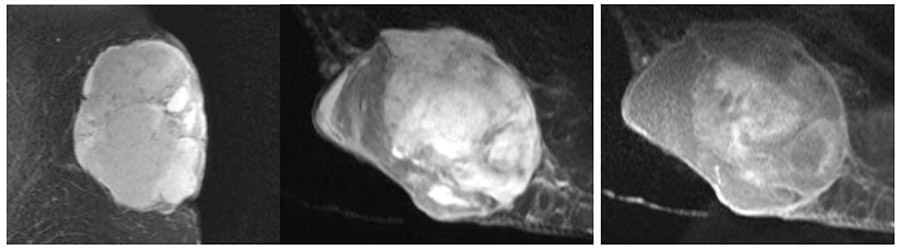

Ameliyat Öncesi: MR’da düzensiz sınırlı heterojen ve yoğun kontrast tutan kitle görülmekte